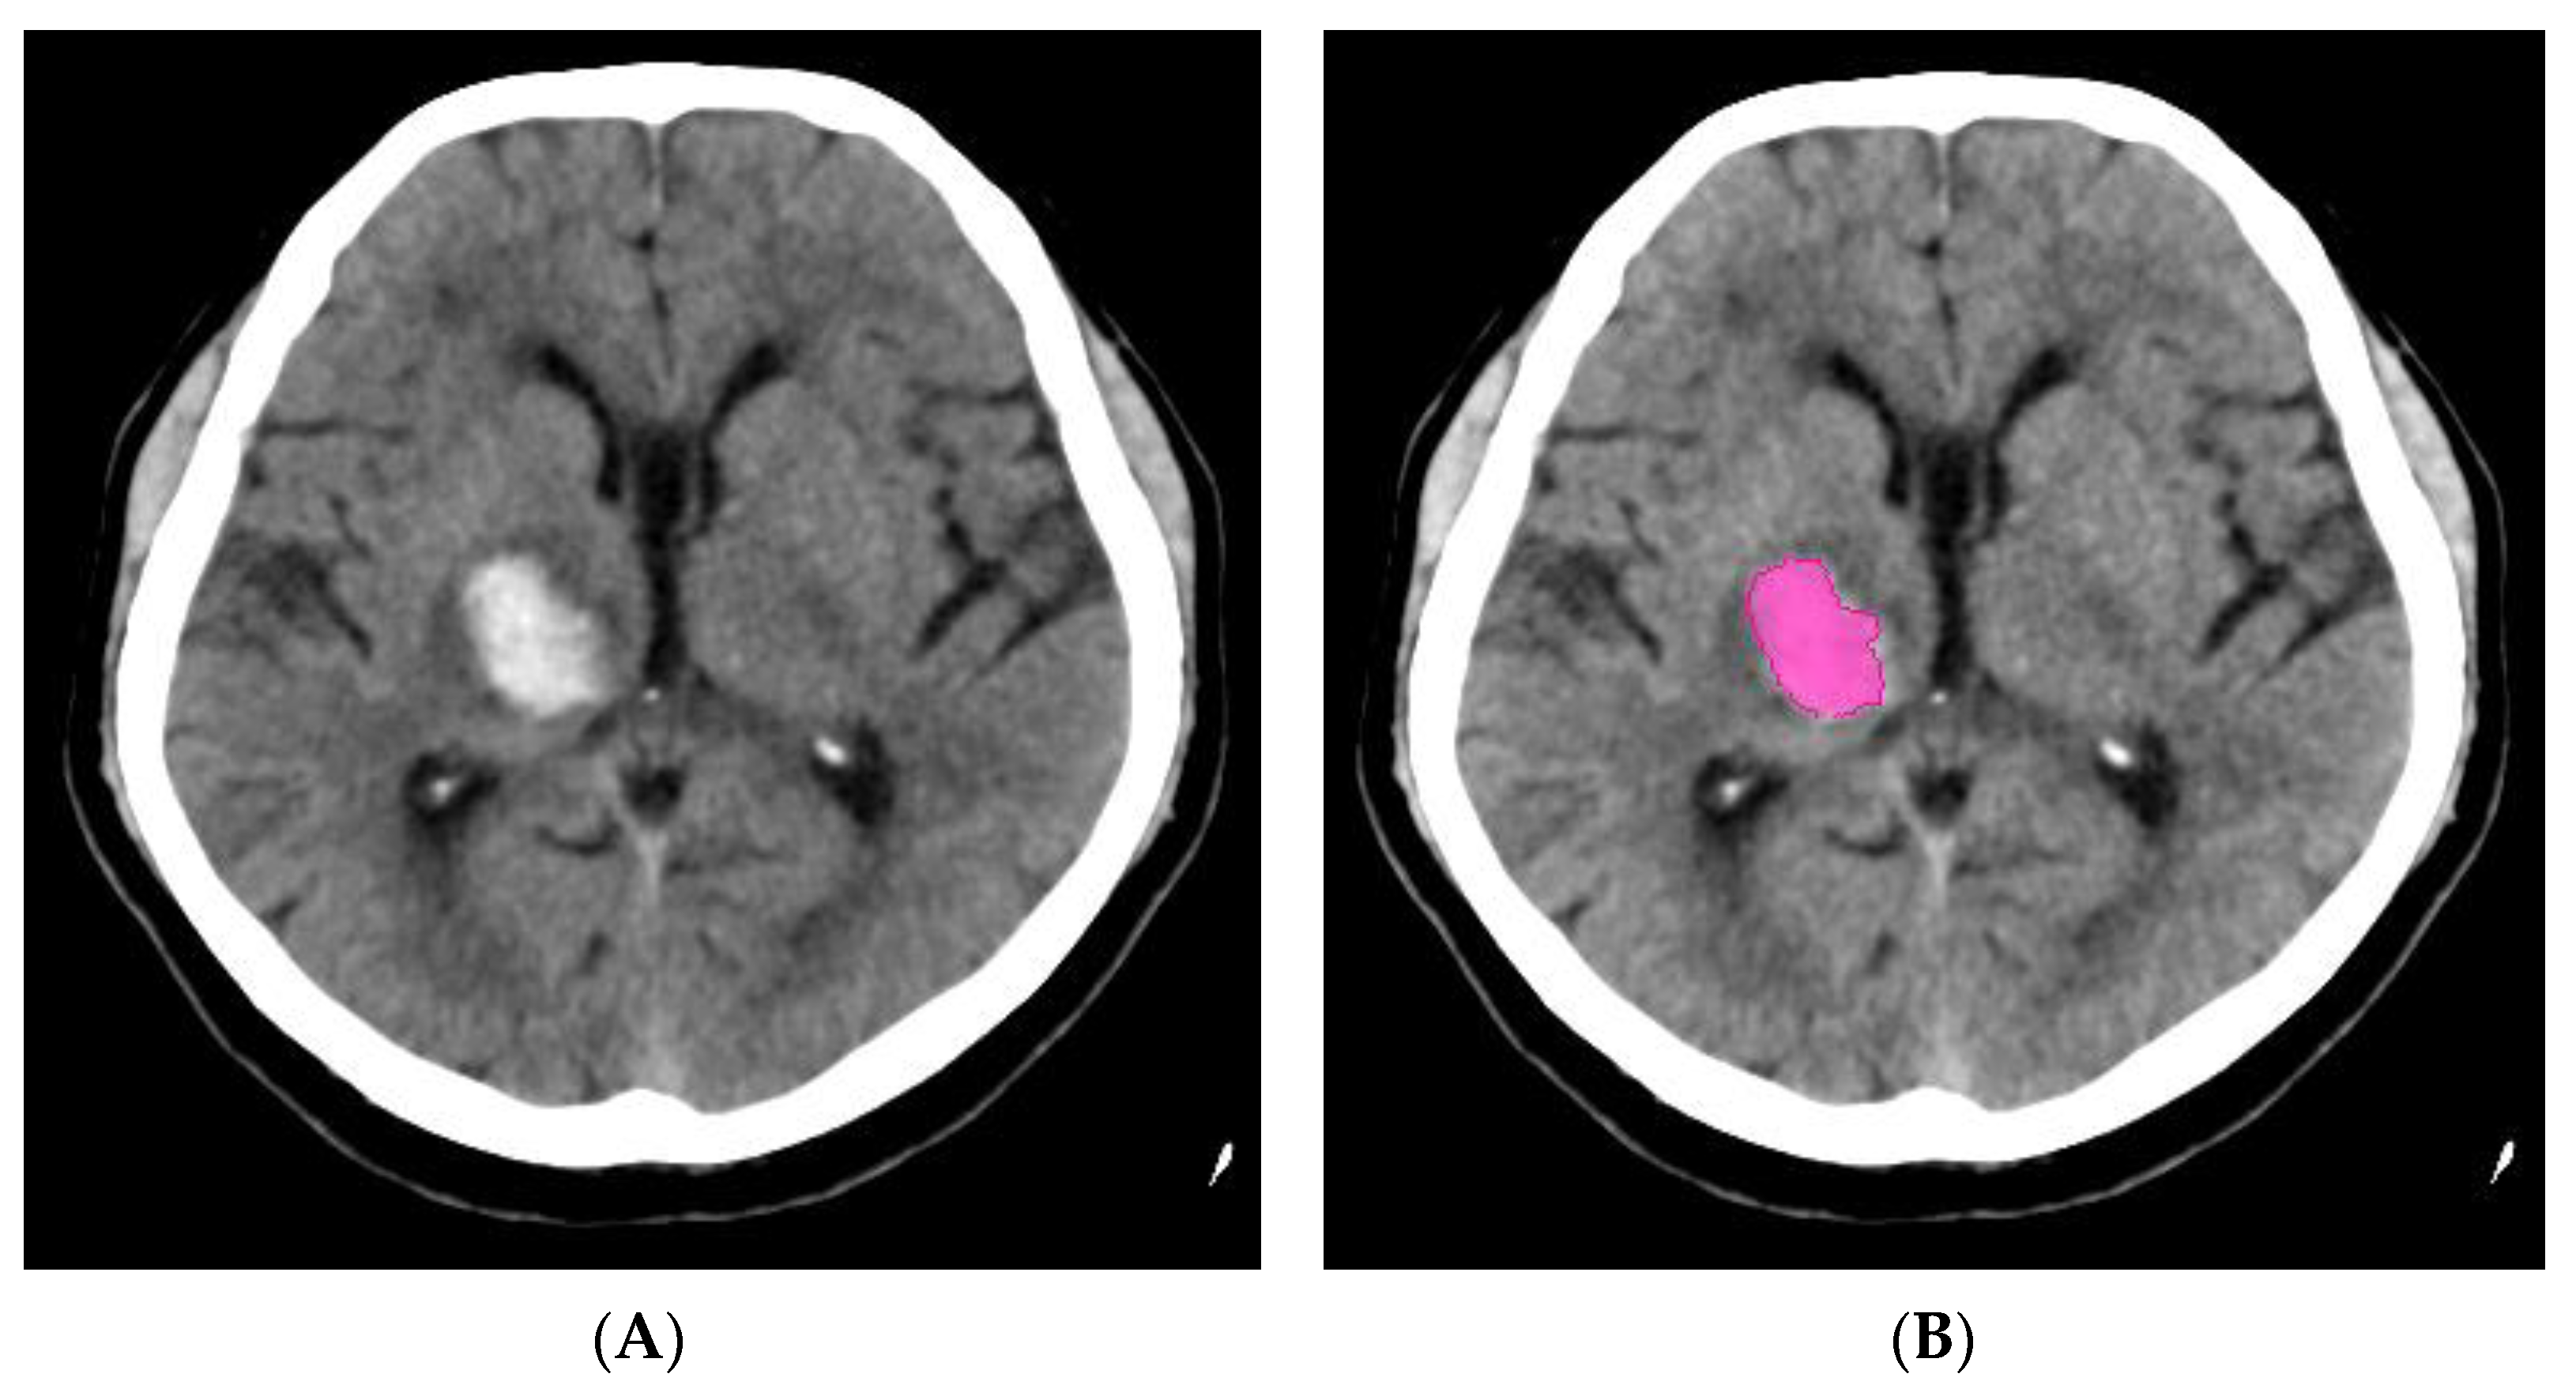

Differential Diagnosis

Prognosis